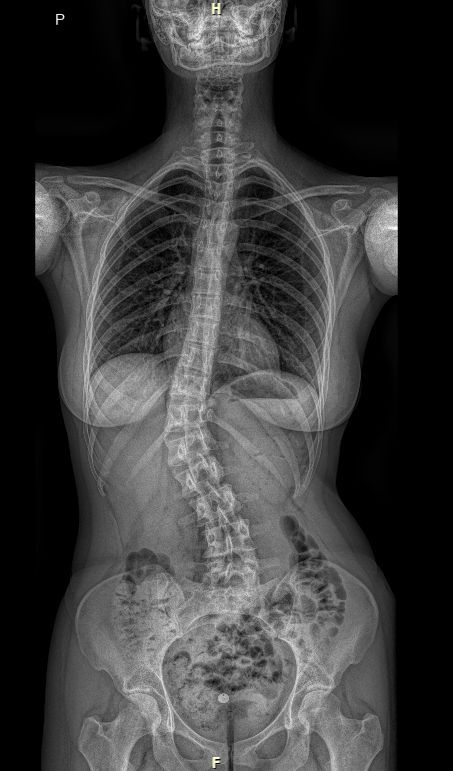

RTG celé páteře (EOS)

Jako první zobrazovací metodu obvykle provádíme RTG, případně EOS. Poskytuje nám obraz páteře v předozadní a boční rovině a umožňuje měřit stupeň zakřivení. RTG provádíme pravidelně na každé kontrole k posouzení vývoje křivky.